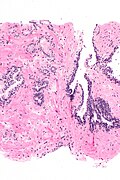

Microscopic

Features:

- Atypical appearing acini - see criteria for prostate adenocarcinoma.

- Limited extent - key feature.

- Less than six glands.†

- † There is no agreed upon minimum number of glands; however, one paper suggests that agreement among experts is low with 5 or less glands.[7]